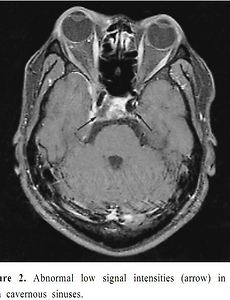

골막하농양(Subperiosteal abscess), 안와농양(Orbital acscess), 해면정맥굴혈전(Cavernous sinus thrombosis) 안와 연조직염(Orbital cellulitis)은, 코곁굴염(sinusitis)눈꺼풀염(blepharitis)눈물주머니염(dacryocystitis)혈행성 전파(hematogenous origin)외상(trauma) 이러한 다양한 원인으로부터 감염이 파급되어 나타나는 대표적인 안와 감염 질환으로 소아에서는 안구돌출의 가장 흔한 원인이 됩니다. 안와 연조직염의 가장흔한 원인은, 코곁굴염, 즉 급성축농증인데, 축농증이 발생한뒤, 염증과 감염이 코의 공간인 부비강에서부터 눈의 공간인 안와 쪽으로 전파되는 것입니다. 이렇게 뼈를 타고 코쪽에서부터 넘어온 감염이, 안와내에 퍼져 있는 것이 안와 연조직염(orbital cellulitis)이고, 안와내로 퍼지지 못하고 안와의 골막하에 고여서 농, 고름이 차는 것이.. 2018. 8. 20.